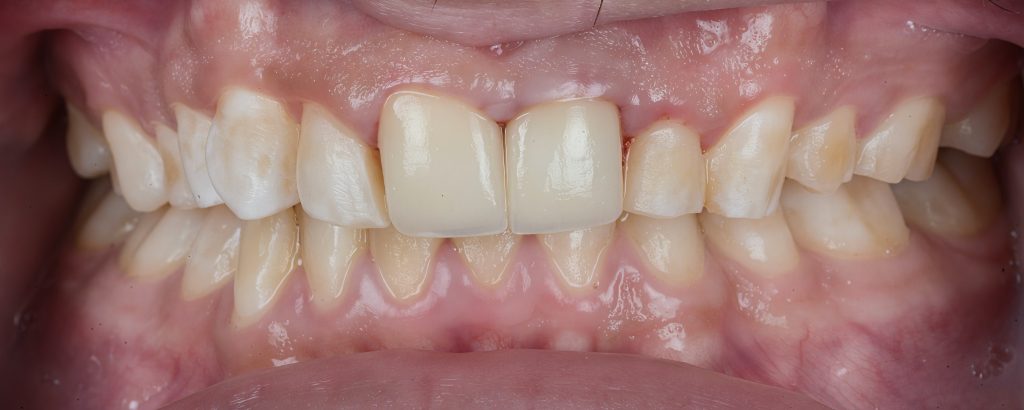

Pre-Operative Assessment

Clinical findings included:

- Irregular lengths and fractured enamel edges

- Poor axial inclination of centrals

- Previous composite restorations discolored and debonded

- Mild gingival inflammation

- Pulpal involvement confirmed radiographically

Primary goals: Restore function, protect remaining tooth structure, correct smile proportions, and achieve long-term stability.